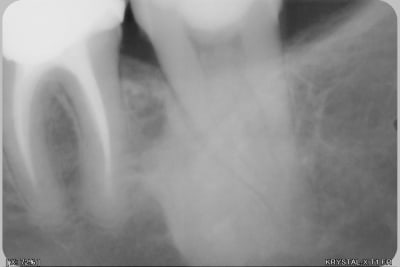

Voila,je vous joins une radio que j'ai prise ce soir sur une 37.

Quelle peut-être la nature de l'image radioopaque en mésial de la dent et quelle devrait-être la conduite à tenir en cas d'extraction (dent fissurée que j'espère sauver)?